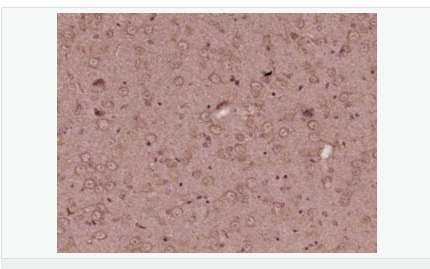

產(chǎn)品介紹KIF13B is also known as Kinesin-like protein GAKIN or GAKIN and is a 1,826 amino acid protein that is widely expressed in tissues, with highest expression in brain and kidney. KIF13B is localized to the cytoplasm, as well as to the cytoskeleton, and is thought to be a microtubule-dependent motor protein which is able to bind to a variety of proteins in order to traffic them to various locations throughout the cell. KIF13B belongs to the kinesin-like protein family and possesses three domains typical of the kinesin-like protein family, namely an N-terminal motor domain with an ATP-binding motif, an FHA domain which is known to bind diverse cargos and a large stalk domain involved in protein-protein binding. Additionally, KIF13B has a microtubule-interacting sequence which is known as the CAP-Gly domain at its C-terminus. The CAP-Gly domain is highly conserved domain among eukaryotes, and in humans, defects in the CAP-Gly domain are implicated in many diseases affecting the trafficking of vesicles, neuromuscular junctions and lysosome proliferation.

產(chǎn)品應(yīng)用WB=1:500-2000 ELISA=1:5000-10000 IHC-P=1:100-500 IHC-F=1:100-500 ICC=1:100-500 IF=1:200-800 (石蠟切片需做抗原修復(fù))

細胞定位細胞漿